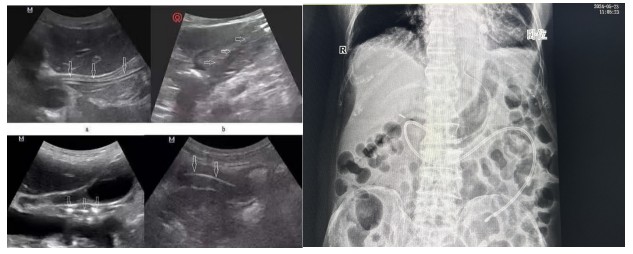

經(jīng)腹部X片驗(yàn)證一個(gè)完美的大“C”呈現(xiàn)出來,確認(rèn)鼻空腸管已經(jīng)達(dá)到指定位置。

B超引導(dǎo)下營(yíng)養(yǎng)管置入術(shù)相比內(nèi)鏡輔助下營(yíng)養(yǎng)管置入,通過二維顯像觀察鼻腸管的位置,無創(chuàng)監(jiān)測(cè),定位準(zhǔn)確,提高了置管的成功率,能有效減少置管給病人帶來的不適體驗(yàn)及不必要的損傷。營(yíng)養(yǎng)支持已成為重癥患者綜合治療重要環(huán)節(jié),對(duì)重癥患者預(yù)后起著關(guān)鍵作用,新喂養(yǎng)途徑的建立,讓腸內(nèi)營(yíng)養(yǎng)支持順利的開展,不僅減少了患者的痛苦,也為重癥營(yíng)養(yǎng)支持治療開辟了一條嶄新的補(bǔ)給通道。